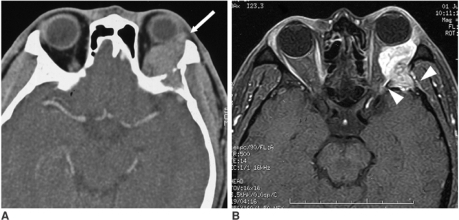

- CT: 골 침범, 석회화 평가

- MRI: 연조직 해상도 우수, 시신경 침범 평가

위치별 감별

| 근원추 내(intraconal) | Cavernous hemangioma, 시신경 종양 |

| 근원추 외(extraconal) | 눈물샘 종양, Dermoid cyst |

주요 안와종양 영상 소견